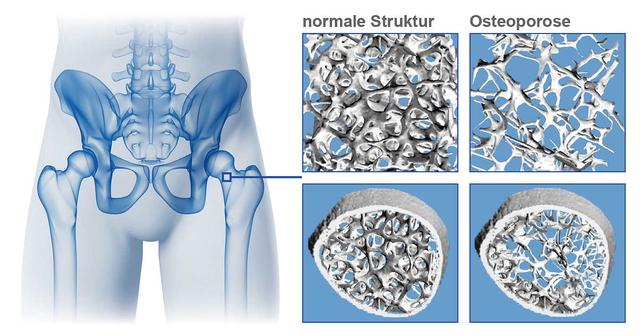

Osteoporose wird gefährlich, wenn der Verlust an Knochenmasse über das normale Maß hinausgeht und der Knochen schneller abbaut als erneuert wird. Dies führt zu porösen Knochen, die weniger stabil sind und leichter brechen können. Besonders gefährlich sind Knochenbrüche in der Wirbelsäule, im Hüft- oder Oberschenkelbereich, da sie mit starken Schmerzen und Einschränkungen der Mobilität einhergehen können.

Mit zunehmendem Alter ist ein gewisser Verlust an Knochenmasse normal. Ab etwa 40 Jahren nimmt die Knochendichte allmählich ab, etwa um ein Prozent pro Jahr. Dieser altersbedingte Knochenschwund ist jedoch nicht zwangsläufig gefährlich oder krankhaft. Erst wenn dieser Verlust über das normale Maß hinausgeht und sich der Abbau beschleunigt, spricht man von Osteoporose.

Ein wichtiger Faktor für die Schwere der Osteoporose ist das Ausmaß des Knochenschwunds. Je mehr Knochenmasse verloren geht, desto poröser und instabiler werden die Knochen. Dadurch steigt das Risiko für Knochenbrüche, insbesondere an stark belasteten Stellen wie Hüfte, Wirbelsäule und Handgelenken.

Der Knochenschwund bei Osteoporose kann zu ernsthaften Komplikationen führen und die Lebensqualität erheblich beeinträchtigen. Wenn die Knochenmasse über das normale Maß hinaus abnimmt und der Knochenabbau schneller als der Aufbau erfolgt, werden die Knochen porös und weniger stabil. Dadurch steigt das Risiko für gefährliche Knochenbrüche deutlich an.